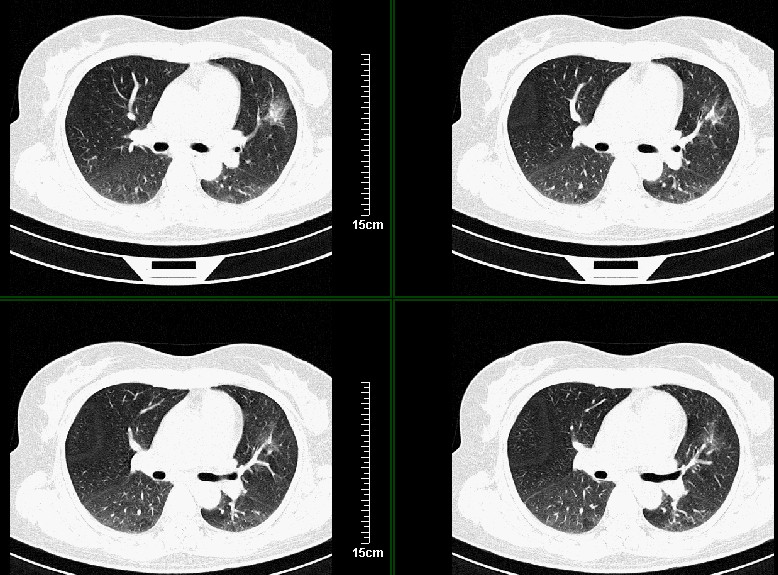

一周之后 复查结果 5mm扫描 40多岁 我们医院的护士

好像和8248是同一个人的病例吧??呵呵,8248大家都认为是感染,现在又都认为是肺癌,图像小了一点,诊断结果就差别这么大。

病灶分明小多多了